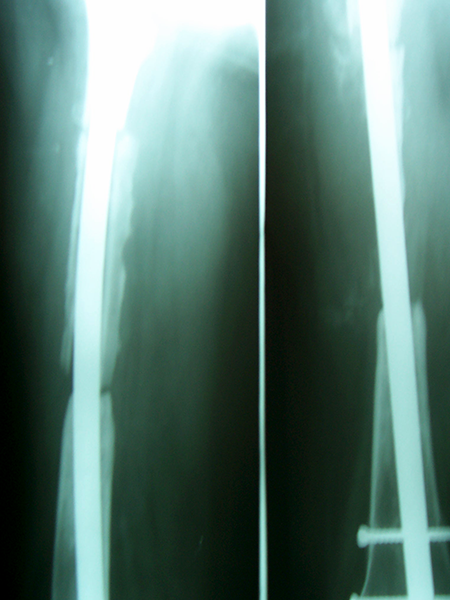

Case:3 Ewings Tibia

Spine Best doctor in satellite|Best Orthopedic Surgeon

Pre-Op

Spine Treatment In Jaipur|Sports Injuries Doctor

Post-Op